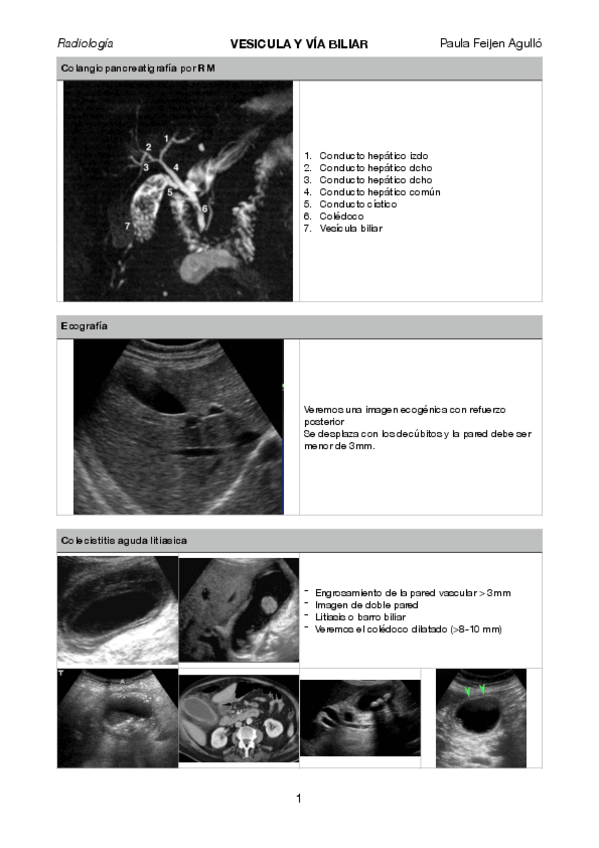

bazo.pdf

via-biliar.pdf